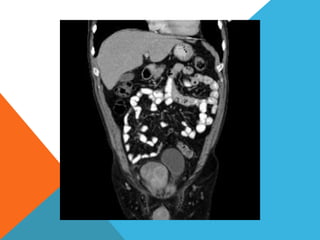

El paciente presentó síntomas de sangrado digestivo y pérdida de peso. Exámenes revelaron gastritis crónica asociada a H. pylori. Un tumor fue descubierto en una colonoscopia normal. La cirugía removió un tumor fibroide solitario, una rara neoplasia mesenquimal que usualmente crece lento y tiene bajo potencial de malignidad. El pronóstico después de la remoción quirúrgica es generalmente bueno.